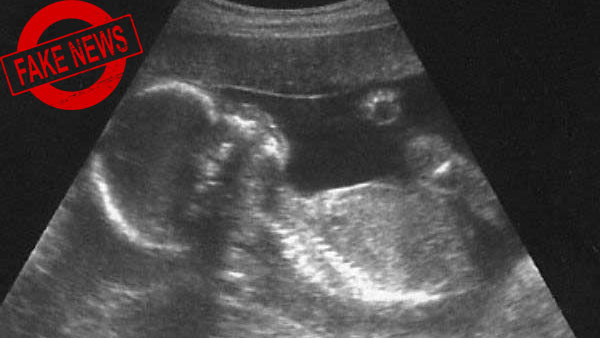

வயிற்றில் இருக்கும் குழந்தை ஆணா, பெண்ணா என்று பார்க்க விதித்த தடை விலக்கப்படவில்லை.. அரசு விளக்கம்

இந்த செய்தி, தவறானது மற்றும் முற்றிலும் யூக அடிப்படையிலானது என்று சுகாதார அமைச்சகம் தெரிவித்துள்ளது.

கருத்தரிப்பதற்கு முன்போ அல்லது அதற்கு பின்னரோ குழந்தையின் பாலினத்தை தேர்ந்தெடுப்பதை, தடைசெய்யும் பிசி & பிஎன்டிடி சட்டத்தை சுகாதாரத்துறை அமைச்சகம் சஸ்பெண்ட் செய்யவில்லை, என்று அமைச்சகம் தெரிவித்துள்ளது.

COVID19 தொற்றுநோய் காரணமாக, நடந்துகொண்டிருக்கும் லாக்டவுனை கருத்தில் கொண்டு, பிசி மற்றும் பிஎன்டிடி விதிகளின் (1996) கீழ் சில விதிகளை ஒத்திவைக்க அல்லது நிறுத்தி வைக்க சுகாதார அமைச்சகம் 2020ம் ஆண்டு, ஏப்ரல் 4ம் தேதி அறிவிப்பை வெளியிட்டதாக குறிப்பிட்ட ஊடகத்தில் செய்தி வெளியானது.

ஏனெனில், இந்த விதிமுறைகளை பதிவு செய்ய அல்லது புதுப்பிக்க விண்ணப்பிக்க வேண்டும். இதற்கு தற்போது அவகாசம் இருக்காது என்பதால் விதிமுறைகளில் தளர்வு கொண்டுவரப்பட்டதாக அந்த செய்தியில் மேலும் கூறப்பட்டது.

ஆனால் இதை மறுத்துள்ள சுகாதாரத்துறை அமைச்சகம், "ஒவ்வொரு அல்ட்ராசவுண்ட் கிளினிக், மரபணு ஆலோசனை மையம், மரபணு ஆய்வகம், மரபணு கிளினிக் மற்றும் இமேஜிங் மையம் ஆகியவை சட்டத்தின் கீழ் பரிந்துரைக்கப்பட்டுள்ளபடி அனைத்து கட்டாய பதிவுகளையும் அன்றாட அடிப்படையில் பராமரிக்க வேண்டும்" என்று மீண்டும் வலியுறுத்தியுள்ளது.